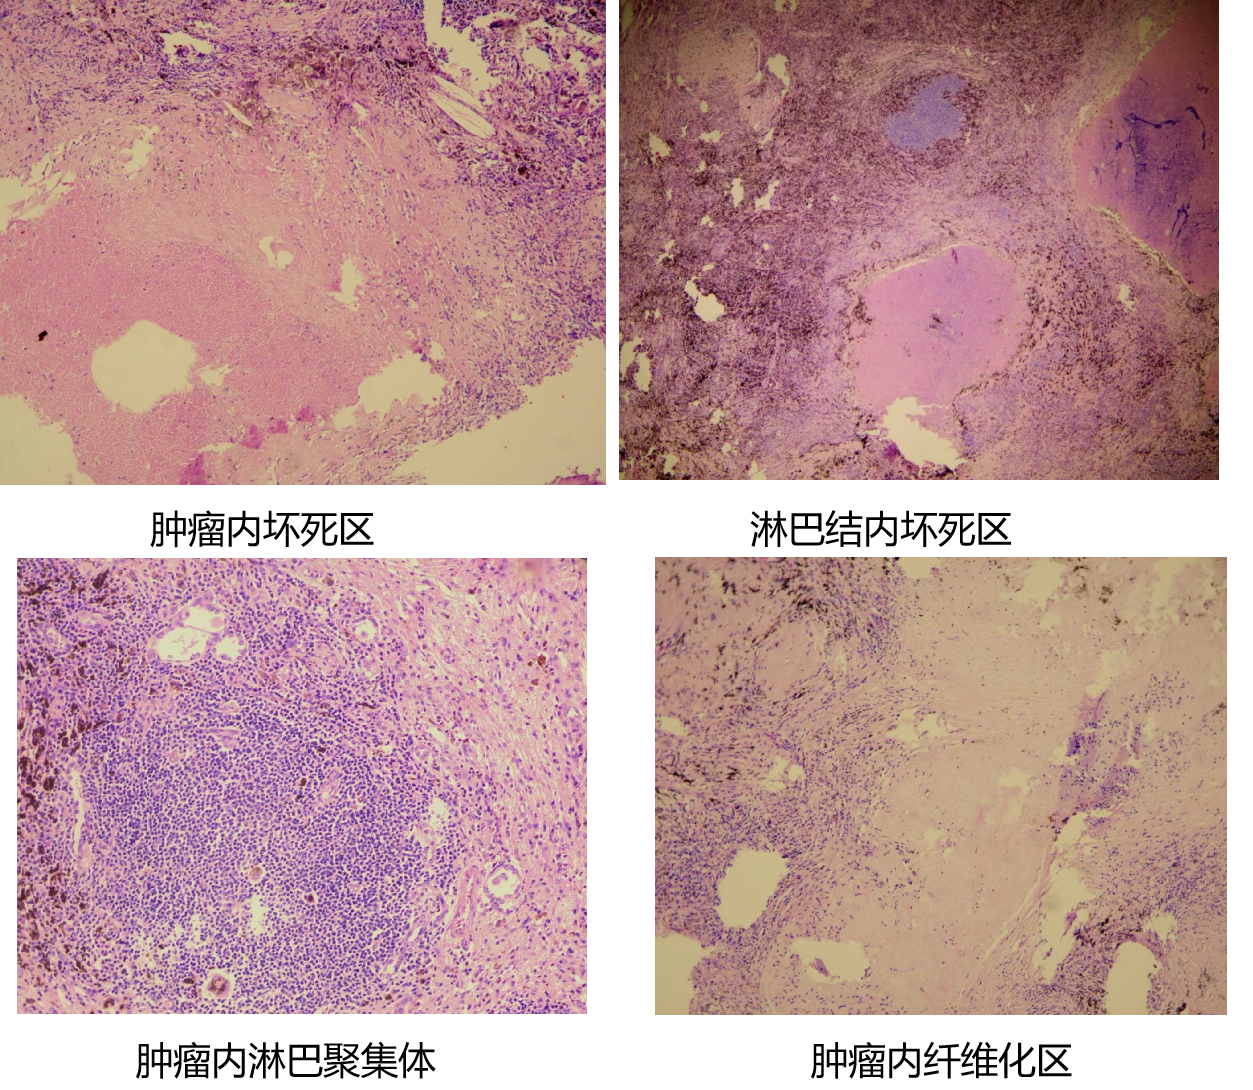

经过4个周期的治疗,向先生的肺部病灶显著缩小,肺门淋巴结也明显缩小(见图3),整个治疗过程中也没有发生明显的不良反应。经过医院MDT(多学科团队协作)会诊,向先生的小细胞肺癌分期成功由IIIA期降至IIA期,大家一致认为已达到手术条件和要求。8月23日新桥医院胸外科在全麻下为向先生做了肺癌根治性切除手术。手术过程顺利,术后的病理结果显示切除的病灶和淋巴结中没有发现肺癌细胞,达到了病理完全缓解(PCR)(见图4)。向先生术后恢复良好,精神状态和气色俱佳,5天后高兴地出院回家。

图4 术后病理切片经仔细检查未发现癌细胞